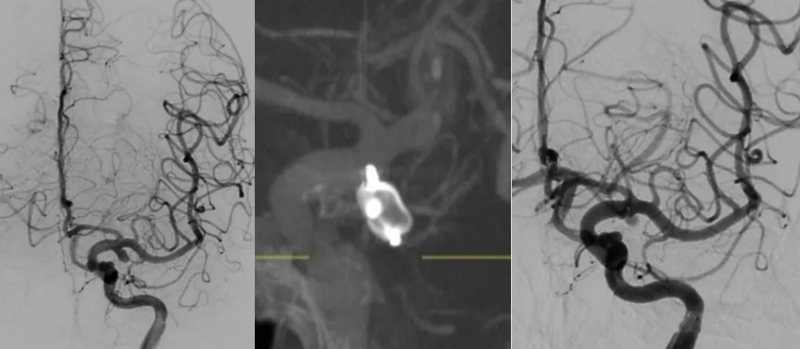

“时间就是生命,必须立即手术!”神经外科专家团队当机立断,提出立即实施脑血管造影,同步准备动脉瘤栓塞手术,术后再行脑室外引流的治疗方案。在征得家属同意后,医院迅速启动急诊手术绿色通道,联动麻醉科、介入导管室等多个科室组建专项救治团队。脑血管造影结果精准定位为左颈内动脉后交通段宽颈动脉瘤,综合考量患者年龄、身体状况等因素,家属最终选择创伤更小、无需二次双抗的WEB扰流装置置入术。

▲术前后造影